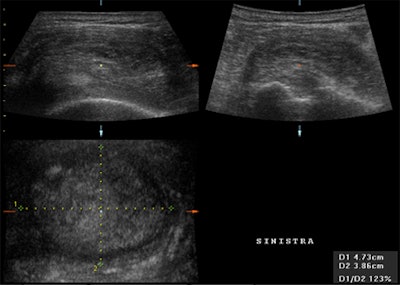

![]() |

| Above and below, post-traumatic multiplanar and enlarged 3D reconstruction of the supraspinatus tendon with small marginal tears that were better depicted using 3D reconstruction. |